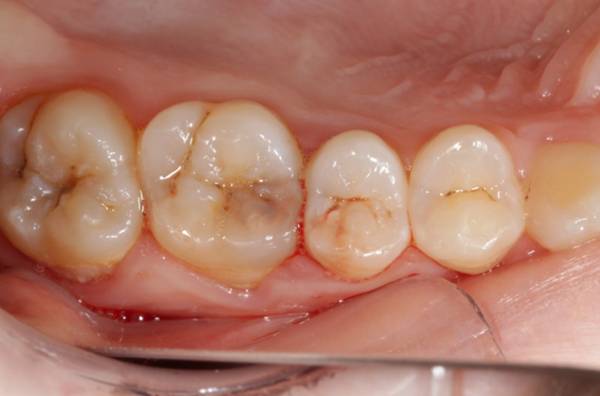

Фото 3. На фотоснимке изображен медленнотекущий кариес в виде затемнения на зубах и без видимых разрушений.